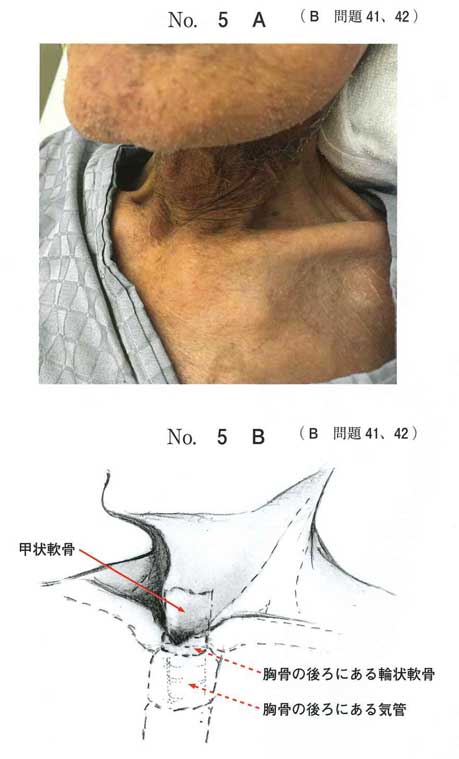

B問題

| タイトル:120B-42 | コメント数:3 |

| 41 | 120B-41 | 3 | |

| 42 | 120B-42 | 3 | |